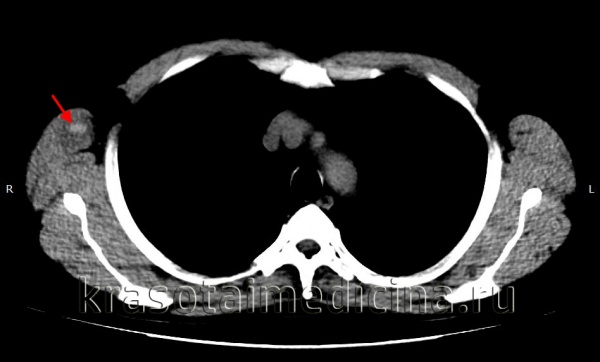

КТ ОГК. Гиперденсное скопление крови в толще мышечного массива грудной стенки справа, окруженное зоной отека.